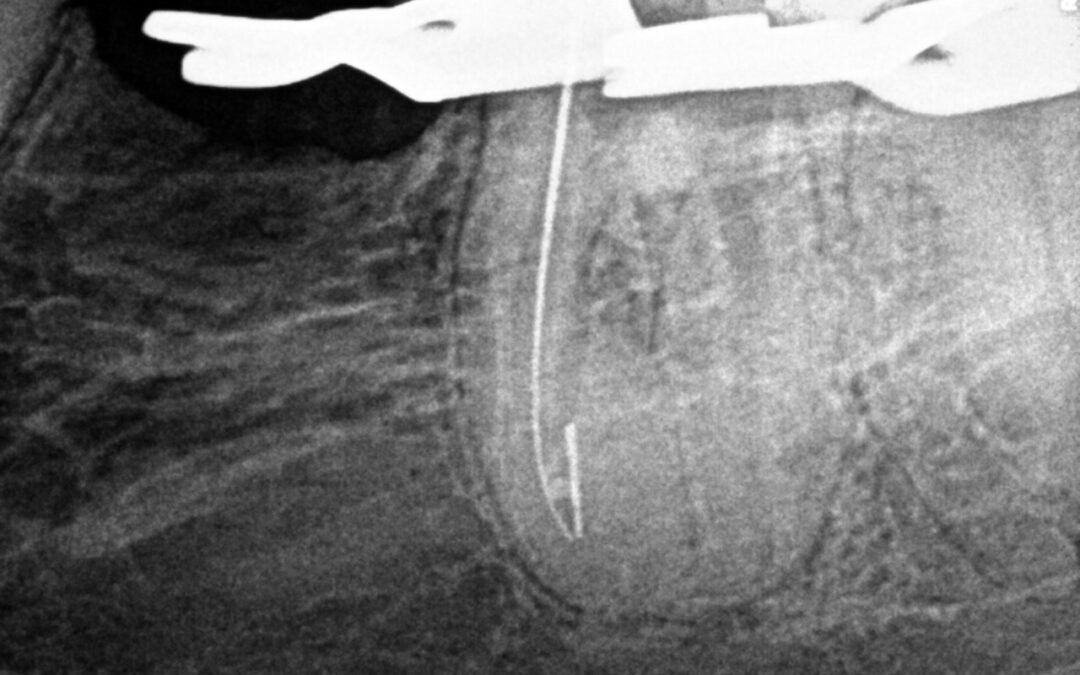

Dente com variação anatômica

Dente com variação anatômica Segundo pré-molar superior esquerdo apresenta canais obturados mesio vestibular disto vestibular e palatino como mostra a radiografia em anexo   Veja esse outro caso complexo de remoção de pino aqui Pesquisar por: Posts recentes Dente...